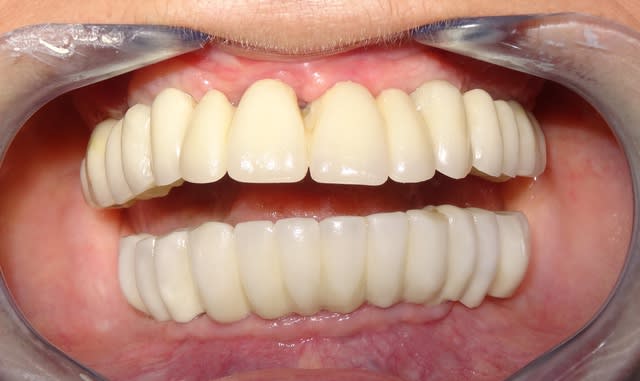

Par contre, le bridge provisoire, je le trouve assez bof (embrasures)mais ce n'est pas très facile à faire en immédiat.

Concernant mon travail (le bridge du haut): on travaille en ce moment à modifier le provisoire à planifier la technique. J'ai fait une greffe sur site infecté en 11 maintenant vous comprenez mieux la gestion tissulaire.

Concernant la mandibule: Ce n'est pas de moi ni la chir ni la prothèse. Le troisième point que je mentionnais était la courbe d'occlusion qui nous a bien fait c---r !!!

Il a fallu composer avec pour des raisons budgétaires. Voilà aussi pourquoi il sera hors de question de passer au définitif directement sans refaire le bas.